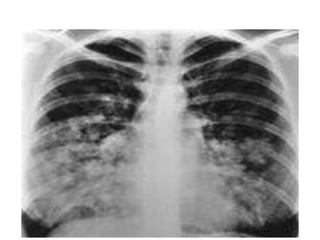

HAPE

Above 4500 m (14,760 ft)

Pathophysiology               Clinical

• Severe pulmonary            • 2 – 4 days after arrival

Hypertension                • SOB

• Some areas pulmonary        • Cough

vascular bed overperfused   • Hemoptysis

• Blood vessel injury         • Dx

• Fluid leak into lung           – Crackles

• Lung edema – water             – Xray

– Worsens gas exchange

HAPE Above 4500 m (14,760 ft) Pathophysiology Clinical • Severe pulmonary • 2 – 4 days after arrival Hypertension • SOB • Some areas pulmonary • Cough vascular bed overperfused • Hemoptysis • Blood vessel injury • Dx • Fluid leak into lung – Crackles • Lung edema – water – Xray – Worsens gas exchange